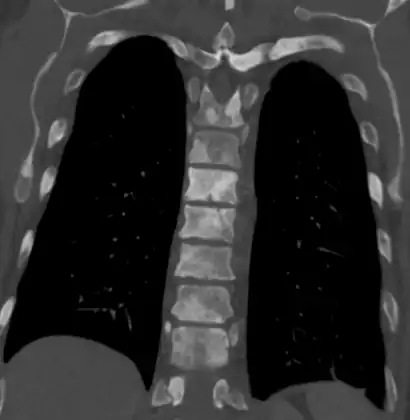

Sclerosis of the bones of the thoracic spine due to prostate cancer metastases (CT image)